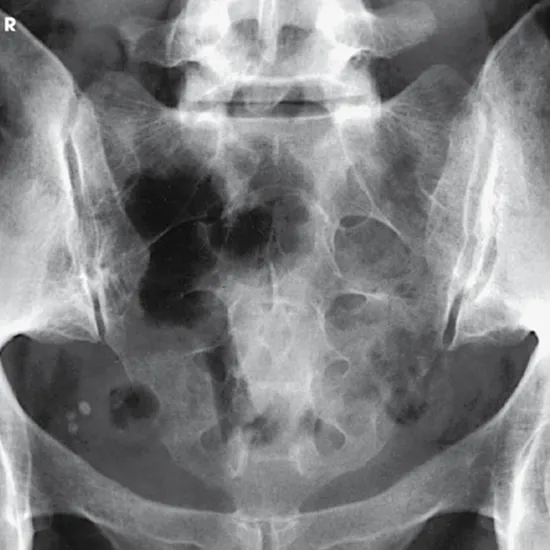

X-rays of the sacroiliac joint are used to see the back region where the spine and pelvis meet (hip bones).

With an X-ray SI Joint PA (Postero-Anterior) View, you can see any breaks, dislocations, or subluxations of the sacroiliac joints and possible inflammation (sacroiliitis) of the sacrum or sacroiliac joints.